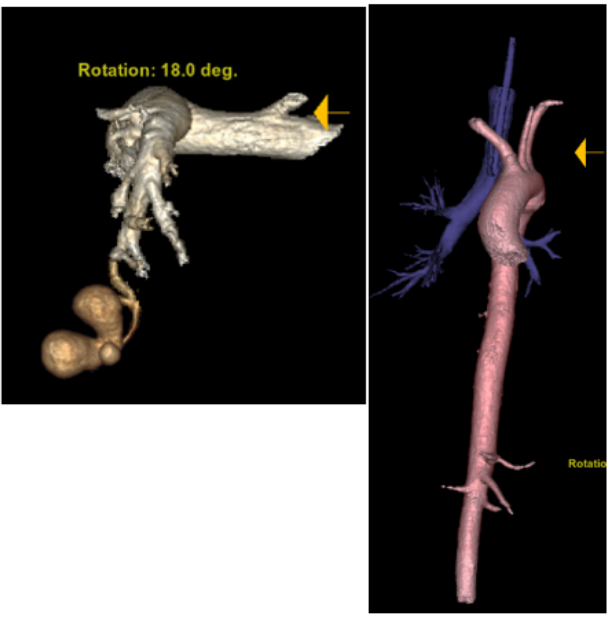

5月5日复查胸部CT:肺渗出病灶较前吸收,右上肺厚壁空洞,左侧胸腔血气胸伴左肺膨胀不全(图7)。支气管动脉CTA示:支气管动脉未见明显异常,未见肺占位;左肺下叶簇状瘤样改变,内见造影剂充盈,边缘光滑清晰,考虑血管改变,三维重建与左肺下叶动脉相连(图8),符合肺动脉瘤诊断。

7  患者胸部CT(2025-05-05)

图片

8  患者支气管动脉CTA(2025-05-05)